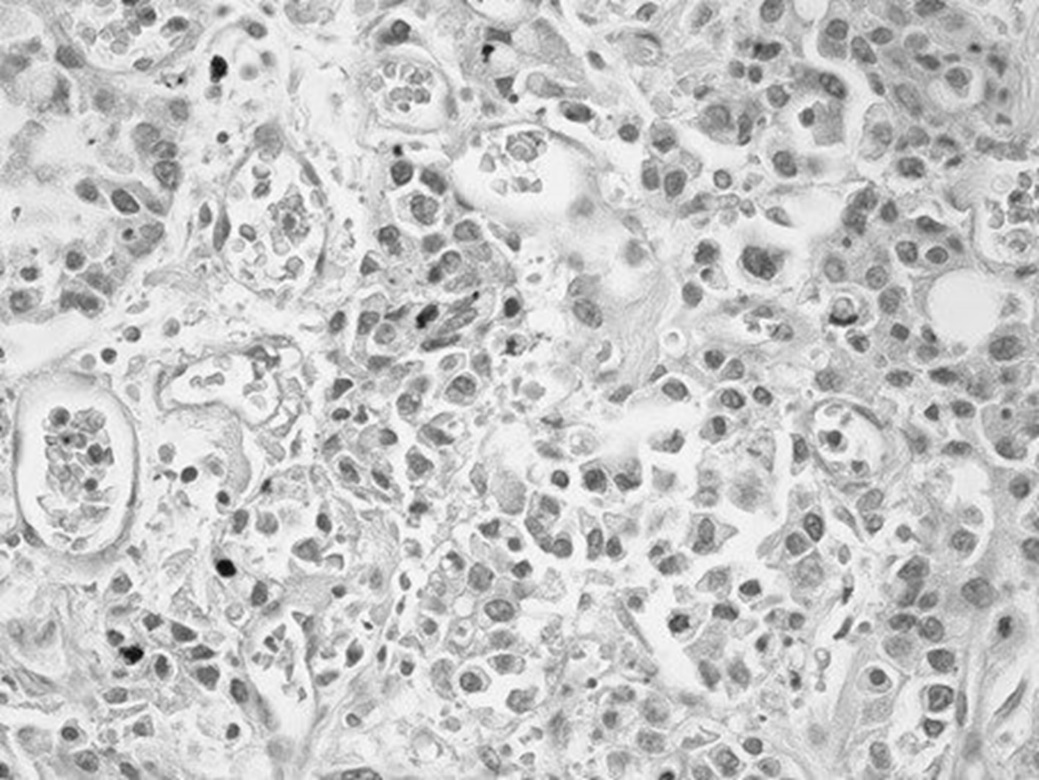

Ниже приводим результат посмертного гистологического исследования ткани печени: «Опухоль представлена полями крупных клеток, не формирующих упорядоченные трабекулярные структуры, с крупными ядрами. Во многих клетках – фигуры митоза, в том числе атипические. Ядра клеток характеризуются выраженным полиморфизмом, многие из них содержат крупные эозинофильные ядрышки. Наряду с атипией и высокой митотической активностью отмечается высокий ядерно-цитоплазматический коэффициент (соотношение площади ядра и цитоплазмы). Клетки располагаются как группами, так и изолированно, разделены узкими прослойками стромы (рис. 2). Опухолевая ткань с обильной васкуляризацией (рис. 3). Во многих сосудах встречаются опухолевые эмболы (рис. 4). Гистологическое заключение: низкодифференцированная гепатоцеллюлярная карцинома (G3), мультифокальный рост опухоли».

Рис. 4. Опухолевые эмболы в сосудах среди ткани опухоли. Окраска гематоксилином и эозином, ув. 400